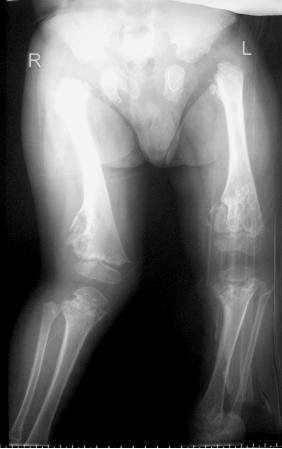

A skeletal survey at the age of 7 years, reformatted coronal spine CT scan showed thoracic scoliosis with significant vertebral disorganization associated with false image of butter-fly like vertebrae of the T8 and L1 and wedging of L2 because of irregular and defective ossification of the vertebral bodies which resembles segmentation defects overwhelmed by extensive enchondromatous lesions along the entire spine and the lacy-like appearance of the iliac crests (Figure 2 [Fig. 2]). Reformatted coronal spinal CT scan showed significant platyspondyly and anisospondyly (irregularly shaped vertebral bodies) in which a unique vertebral disorganization malformation complex is notable. Specific feature – chondromatose nodes in vertebral bodies (bony “defects” in anterior aspects, mostly – at thoracic level) (Figure 3 [Fig. 3]). Antero-posterior (AP) standing radiograph showed hypoplastic iliac bones associated with severe epiphyseal dysplasia and enchondroma-like lesions metaphyseal changes with significant metaphyseal expansion and radiolucency of the inferior femora. Note the windswept lower limb deformity (abnormal valgus deformity in one knee in association with varus in the other) (Figure 4 [Fig. 4]). Contrast arthgrography of the hips demonstrates spherical shape of the femoral heads with severe delayed ossification. Congruency of the hip joints is normal, cartilaginous acetabular coverage is sufficient. Short femoral necks (more severe on the left side with secondary decreased neck-shaft angle) are notable (Figure 5 [Fig. 5]). Contrast arthrography of the hips was done to assess cartilaginous components of the hip joints as a part of the previous pre-operative protocol which was standard in our clinic for children with severe hip instability. Now we believe that MRI would be less invasive and a more useful investigation in such a case. Nevertheless our data demonstrates spherical shape of the femoral heads with severe delayed ossification. Congruency of the hip joints is normal, cartilaginous acetabular coverage is sufficient.

Figure 4: AP standing radiograph showed hypoplastic iliac bones associated with severe epiphyseal dysplasia and enchondroma-like metaphyseal changes with significant metaphyseal expansion and radiolucency of the inferior femora. Note the windswept lower limb deformity (abnormal valgus deformity in one knee in association with varus in the other).